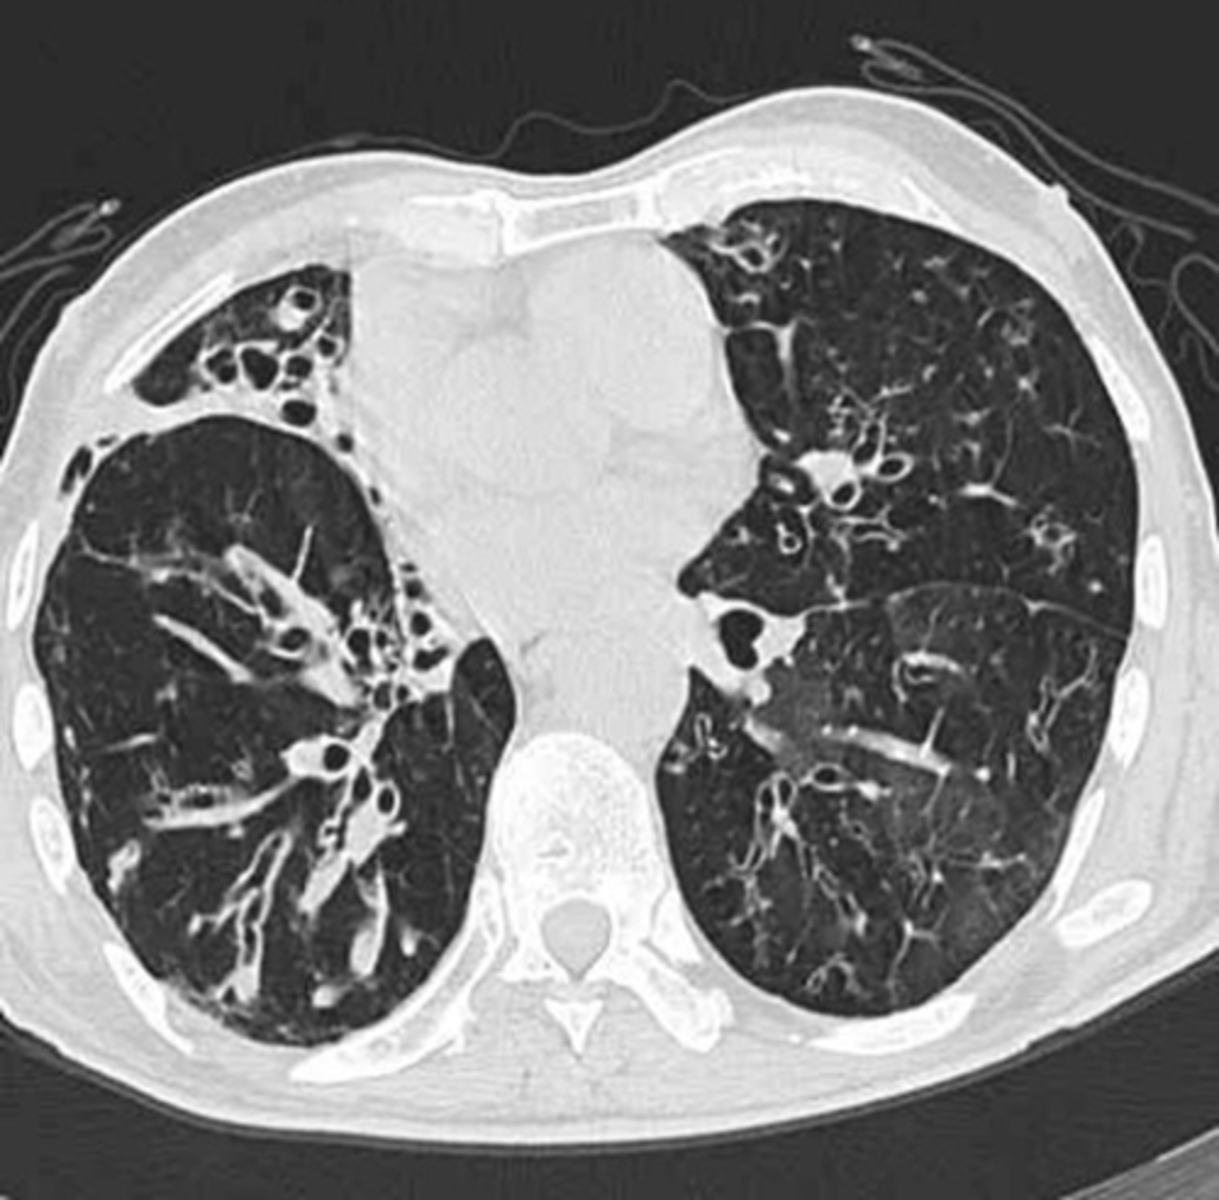

Bronchiectasis

Dz: IRREVERSIBLE focal bronchial dilation, usually accompanied by chronic infection & associated with diverse conditions, some congenital or hereditary

Cause: Obstruction/Poor Drainage

***Cystic Fibrosis (M/C)***, FB, Infection

Sx:

-Persistent cough with early morning sputum

-Productive cough increased with exercise/position change

-Sinusitis

-Clubbing

-Moist rales/rhonchi

-Hemoptysis later

Labs: Culture (H. Flu common infection)

-CXR (bronchovascular markings/atelectasis)

-CT

-PFTs (Obstructive pattern)

Tx:

-Abx/Tx underlying dz

-Physiotherapy

-Surgery to remove affected lobe/area

-Vaccines